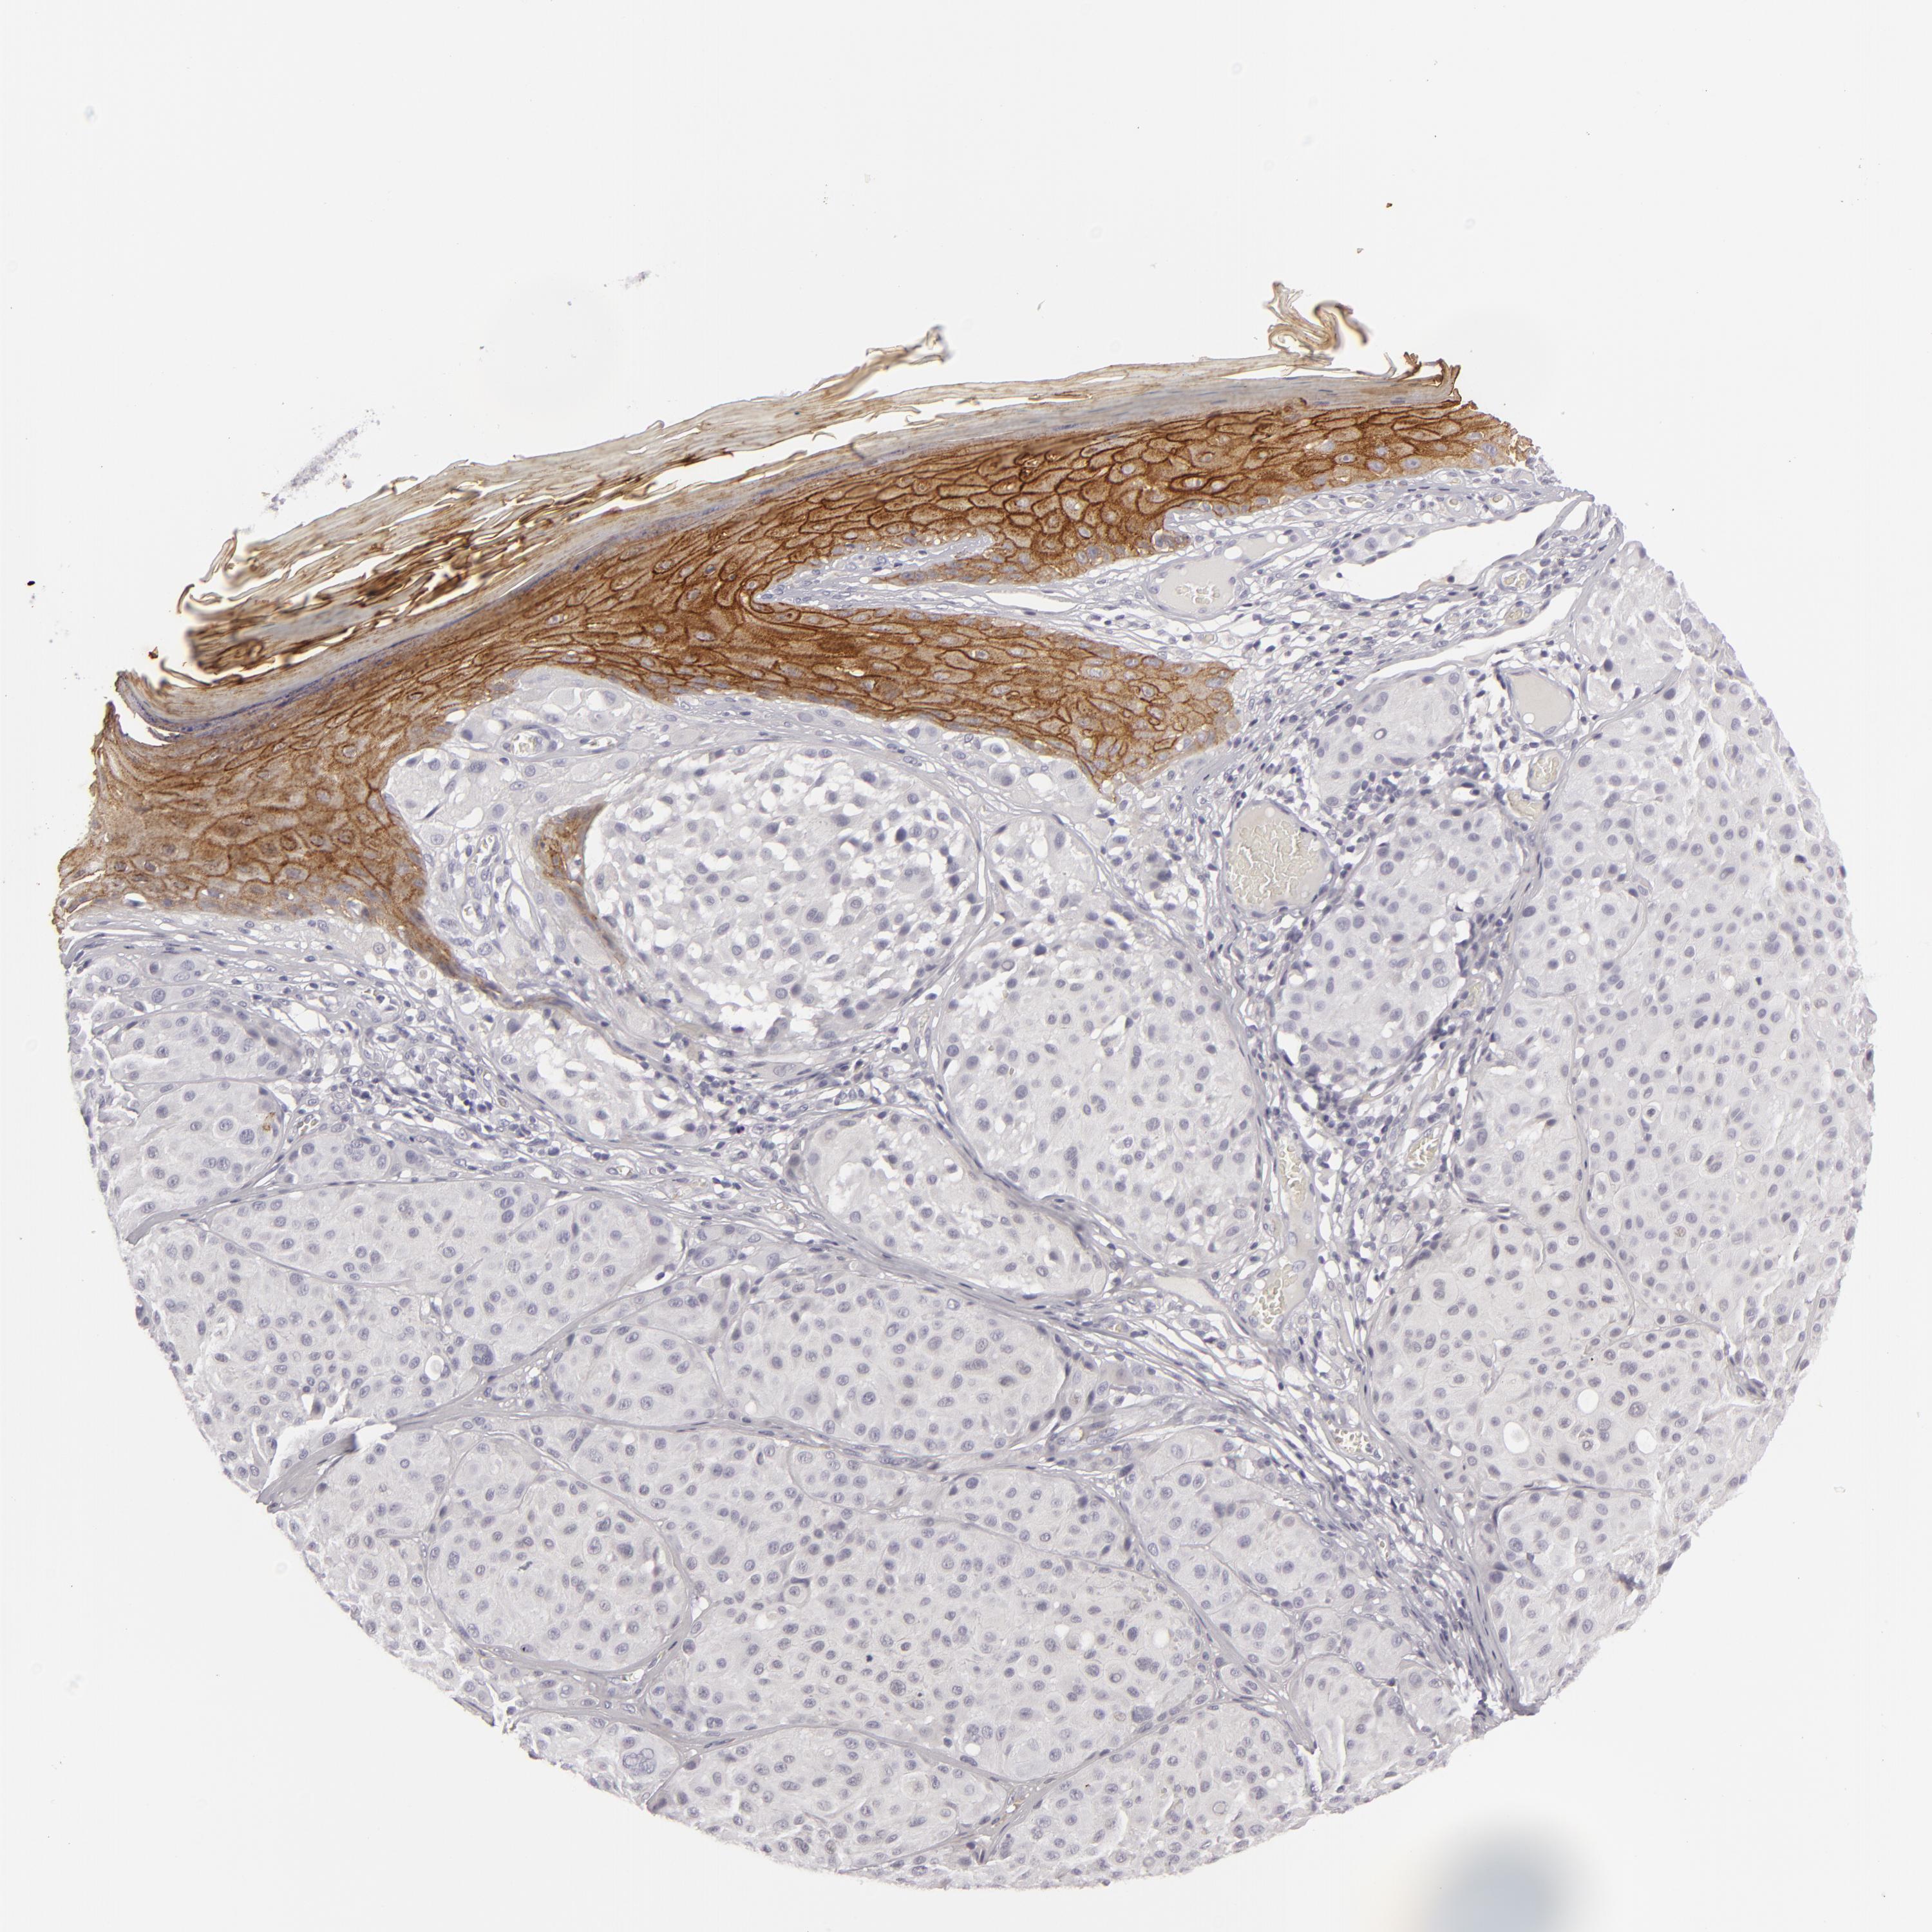

MELANOMA - Protein expressioni

A mouse-over function shows sample information and annotation data. Click on an image to view it in a full screen mode. Samples can be filtered based on level of antibody staining by selecting one or several of the following categories: high, medium, low and not detected. The assay and annotation is described here.

Note that samples used for immunohistochemistry by the Human Protein Atlas do not correspond to samples in the TCGA dataset.

Antibody stainingi

Antibody staining in the annotated cell types in the current human tissue is reported as not detected, low, medium, or high, based on conventional immunohistochemistry profiling in selected tissues. This score is based on the combination of the staining intensity and fraction of stained cells.

Each image is clickable and will lead to virtual microscopy that enables deeper exploration of all samples and also displays staining intensity scores, fraction scores and subcellular localization as well as patient and tissue information for each sample.

Antibody HPA032047

Antibody CAB002139

Staining

High

Medium

Low

Not detected

Intensity

Strong

Moderate

Weak

Negative

Quantity

>75%

75%-25%

<25%

None

Location

Nuclear

Cytoplasmic/membranous

Cytoplasmic/membranous,nuclear

Malignant melanoma, NOS